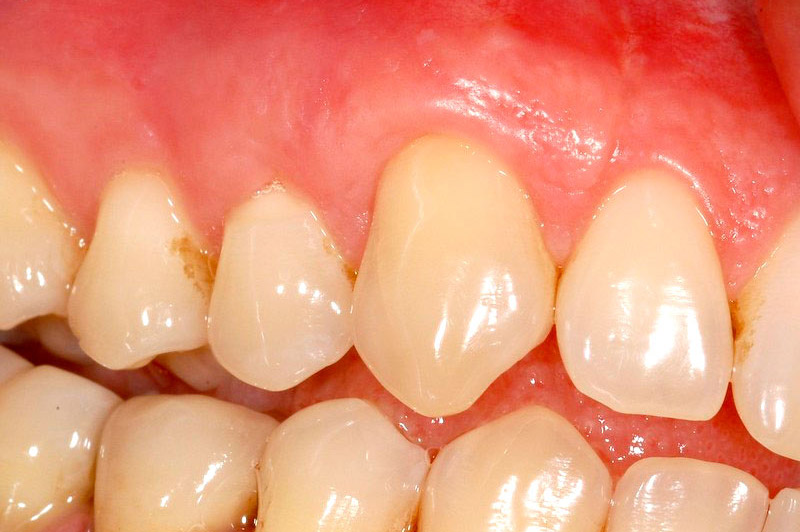

Situazione-parodontale-prima-dell-intervento

Situazione parodontale prima dell’intervento